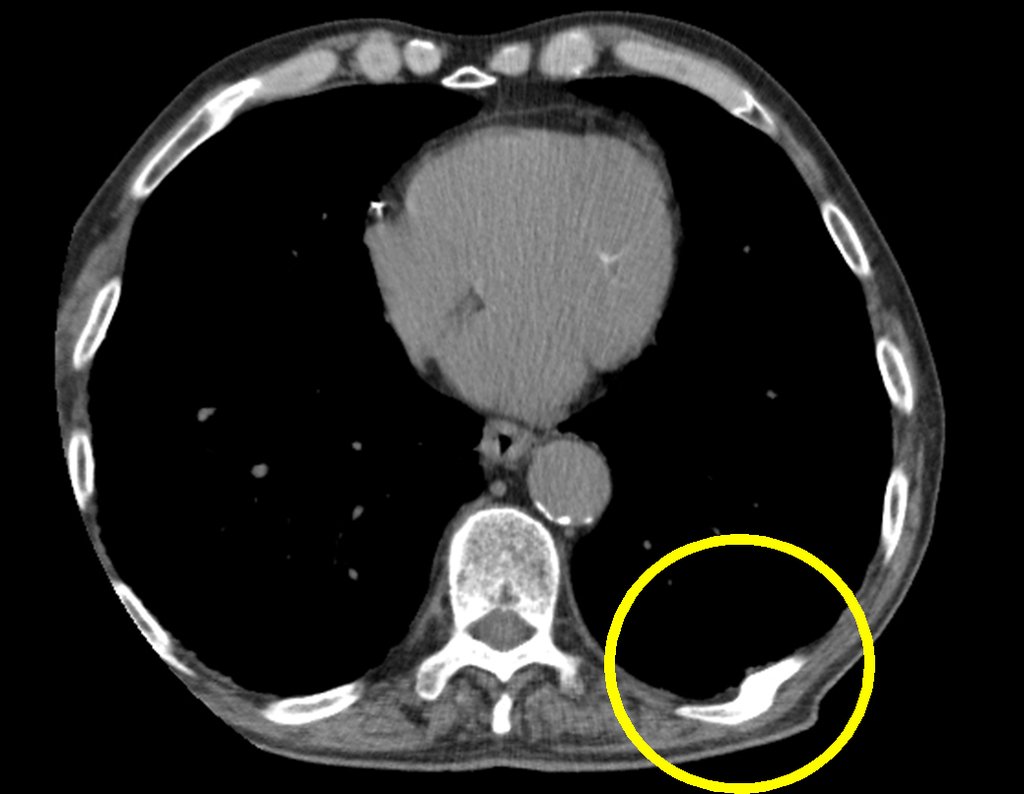

A tomografia axial de tórax evidenciou características de um pulmão de fumante crônico, com áreas de teleangiectasia, congestão vascular e enfisema pulmonar. Entretanto, a tomografia não confirmou a presença do nódulo pulmonar observado nas radiografias iniciais. Em vez disso, foram encontradas alterações no nono e décimo arco costal posterior esquerdo, sugerindo um calo de fratura.

Na análise cuidadosa, das imagens desta tomografia, não se encontrou a área condensante, observada nas radiografias, que sugeria a presença de nódulo primário no parênquima pulmonar do lobo inferior do pulmão esquerdo !?.

Foi encontrado, entretanto, alteração no 90 e 100 arco costal posterior esquerdo, figuras 5 e 6.